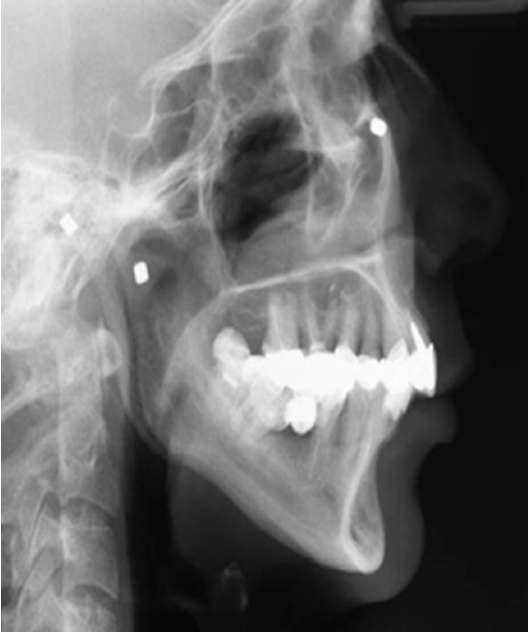

outline studies done by Björk in Copenhagen in the 1950-60s

longitudinal studies

using metal implants in the jaws to study growth

done because sequential radiographs had no reliable reference point so metal pins were inserted as a reference point instead

how was growth observed in Björk’s studies

can see internal rotation in the core of the mandible relative to the cranial base

done by superimposing serial radiographs with metal implants

masked by surface apposition and resorption

Björk’s findings pt. 1

majority had an ‘anterior’ rotation

mandibular plane angle decreases by 2-4°

increasing overbite

more skeletal class III occlusion (underbite)

radiograph and clinical image showing anterior growth rotation of mandible

Björk’s findings pt. 2

minority had a ‘posterior’ rotation

mandibular plane angle increases » anterior open bite

more skeletal class II occlusion

radiograph and clinical image showing psoterior growth rotation of mandible